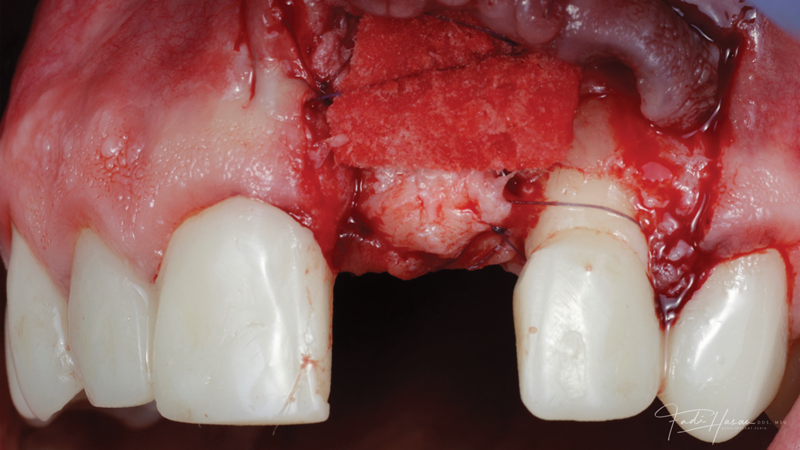

The patient in this case had undergone implant therapy at the site of tooth No. 9 and was restored with a cement-retained restoration more than 5 years prior. At presentation, the site demonstrated a peri-implant soft-tissue dehiscence that extended approximately 3-mm apical to the gingival margin of tooth No. 8. Thin and erythematous marginal tissue was evident at the zenith (Figure 2). The crown was removed, and a partial thickness flap was reflected using a papilla-sparing incision design. This revealed that the implant was positioned too far facially and that its body was visible through a very thin layer of bone (Figure 3 and Figure 4). The first objective of treatment was to minimize the facial extent of the emerging abutment and crown. To accomplish this, the facially positioned abutment and implant crown margin were both recontoured. The second treatment objective was to provide additional supracrestal soft tissue that would more adequately maintain the peri-implant margin. The tuberosity was selected as a donor site due to its dense, high-quality connective tissue, low propensity for shrinkage, and association with minimal patient discomfort. Once the graft was secured (Figure 5 through Figure 7), the flap was coronally positioned (Figure 8). After a healing period of 2 weeks, the margin of tooth No. 9 exhibited an ideal position in relation to its contralateral counterpart and demonstrated increased soft tissue thickness (Figure 9). Three months postoperatively, further healing had improved the esthetics and the position of the margin had been maintained (Figure 10).

(12.) Flap reflection to assess the position of the coronal aspect of the implant and facilitate soft-tissue grafting.

Figure 12